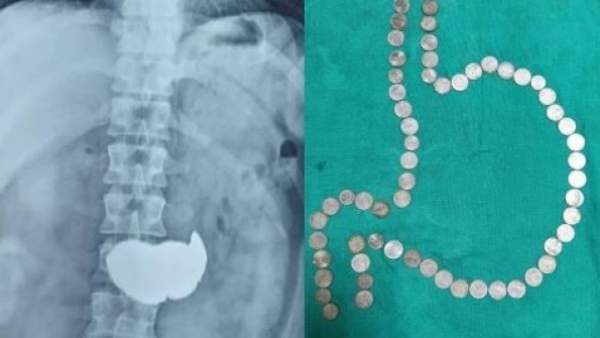

வயிற்றில் 63 நாணயங்கள்…. ஷாக்கான மருத்துவர்கள்…. பெரும் அதிர்ச்சி சம்பவம்…..!!!! 🕑 Mon, 01 Aug 2022

வயிற்றில் 63 நாணயங்கள்…. ஷாக்கான மருத்துவர்கள்…. பெரும் அதிர்ச்சி சம்பவம்…..!!!!

இளைஞர் ஒருவரின் வயிற்றில் இருந்து 63 ஒரு ரூபாய் நாணயங்கள் வெளியே எடுக்கப்பட்ட சம்பவம் ராஜஸ்தானில் நிகழ்ந்துள்ளது. ஜோத்பூரை சேர்ந்த இளைஞர் ஒருவர்